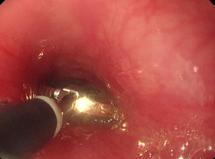

当日,妈妈带着月月来到彩虹医院呼吸二科门诊。呼吸二科副主任、主治医师张亚乐和医院重症医学科主治医师史斐娟根据患者描述,首先拍胸片后发现有纵膈移位,做CT查看。从CT显示的图像上发现,在小月月左侧下方支气管里有异物,管腔变窄。而月月妈妈贾女士回忆,孩子大年初一大人吃花生的时候,孩子有抓的动作,把花生壳咬碎了,当时在孩子嘴里也没有发现异物,所以就没有在意。当检查结果显示有异物,月月妈妈才想起来有这么回事。确定了气管里花生壳的位置后,张亚乐和史斐娟通过支气管镜,在月月全麻状态下,手术不到10分钟,用异物钳将这小半颗花生壳取了出来。术后月月的咳嗽、憋喘等症状顿时好转。

医生利用世界上最先进的设备支气管镜将卡在气管内的花生壳取出,及时救了孩子一命,提起“鬼门关”前走的这一遭,月月一家人仍心有余悸。2月26日,月月已经出院回家。临走医生嘱咐要加强对孩子的日常护理,一个月后进行复查。而月月妈妈更是感激不尽。

孩子家长感觉不妙,2月25日一大早,将孩子送到咸阳市彩虹医院就诊。经过CT检查,医生发现孩子主支气管有异物,是一整颗瓜子,必须尽快将异物取出。情况比较危急,医院呼吸二科副主任、主治医师张亚乐和医院重症医学科主治医师史斐娟当日下午就经过支气管镜将卡在主气管内的整颗西瓜子成功取出。